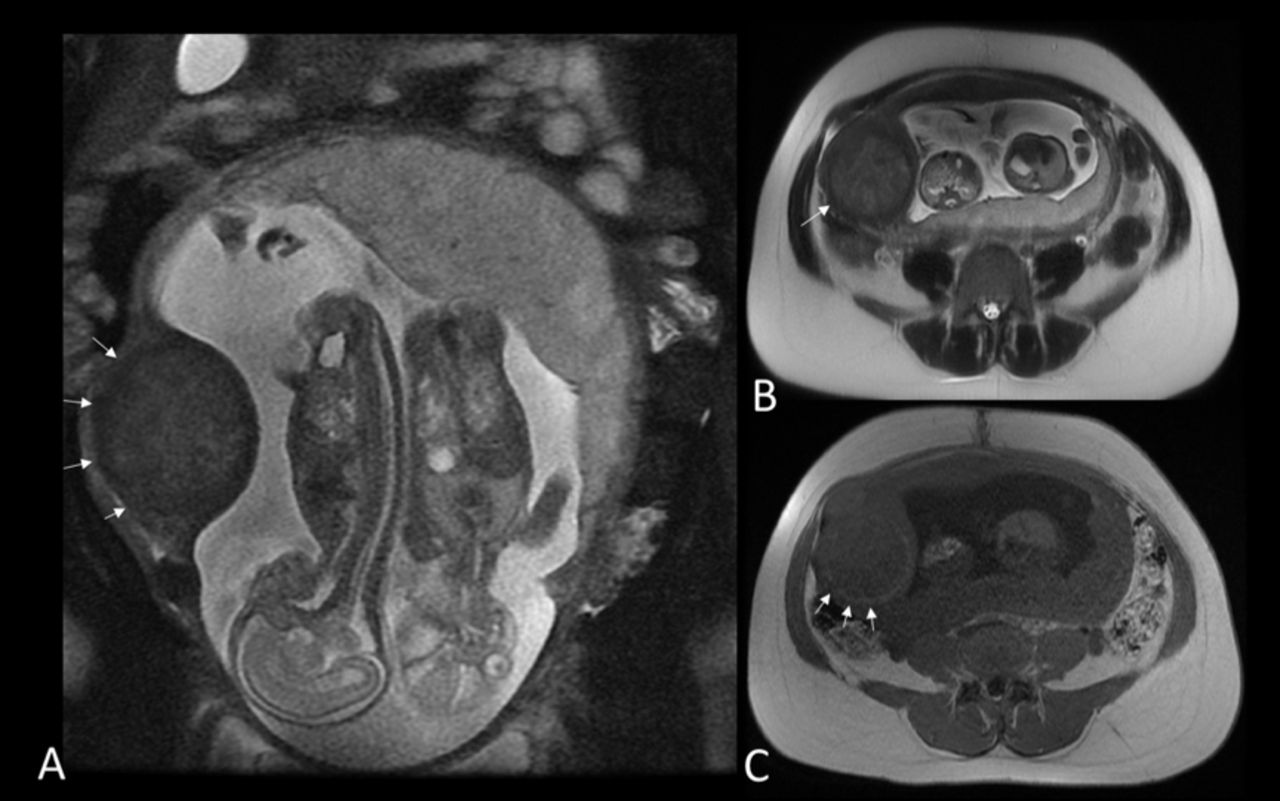

还有一种情况为腹腔妊娠,它分原发性和继发性两种。由于受精卵在腹腔内迷失方向,经过“千山万水”的艰难跋涉最后着床于某脏器上,尤以脾脏为多。因受精卵地处“异域”,待生长发育到一程度之后,“生活”就难以维持了,多数以失败而告终。继发性腹腔妊娠是输卵管妊娠的一种特殊转归。当输卵管妊娠破裂时由于绒毛受伤不多,大部分绒毛仍固定在原来的附着处,胚胎能继续生存发展成为腹腔妊娠。多数孕卵因地处“他乡”,又易出现故障而中途夭折,极个别能生长到足月,经剖腹取出而活下来。